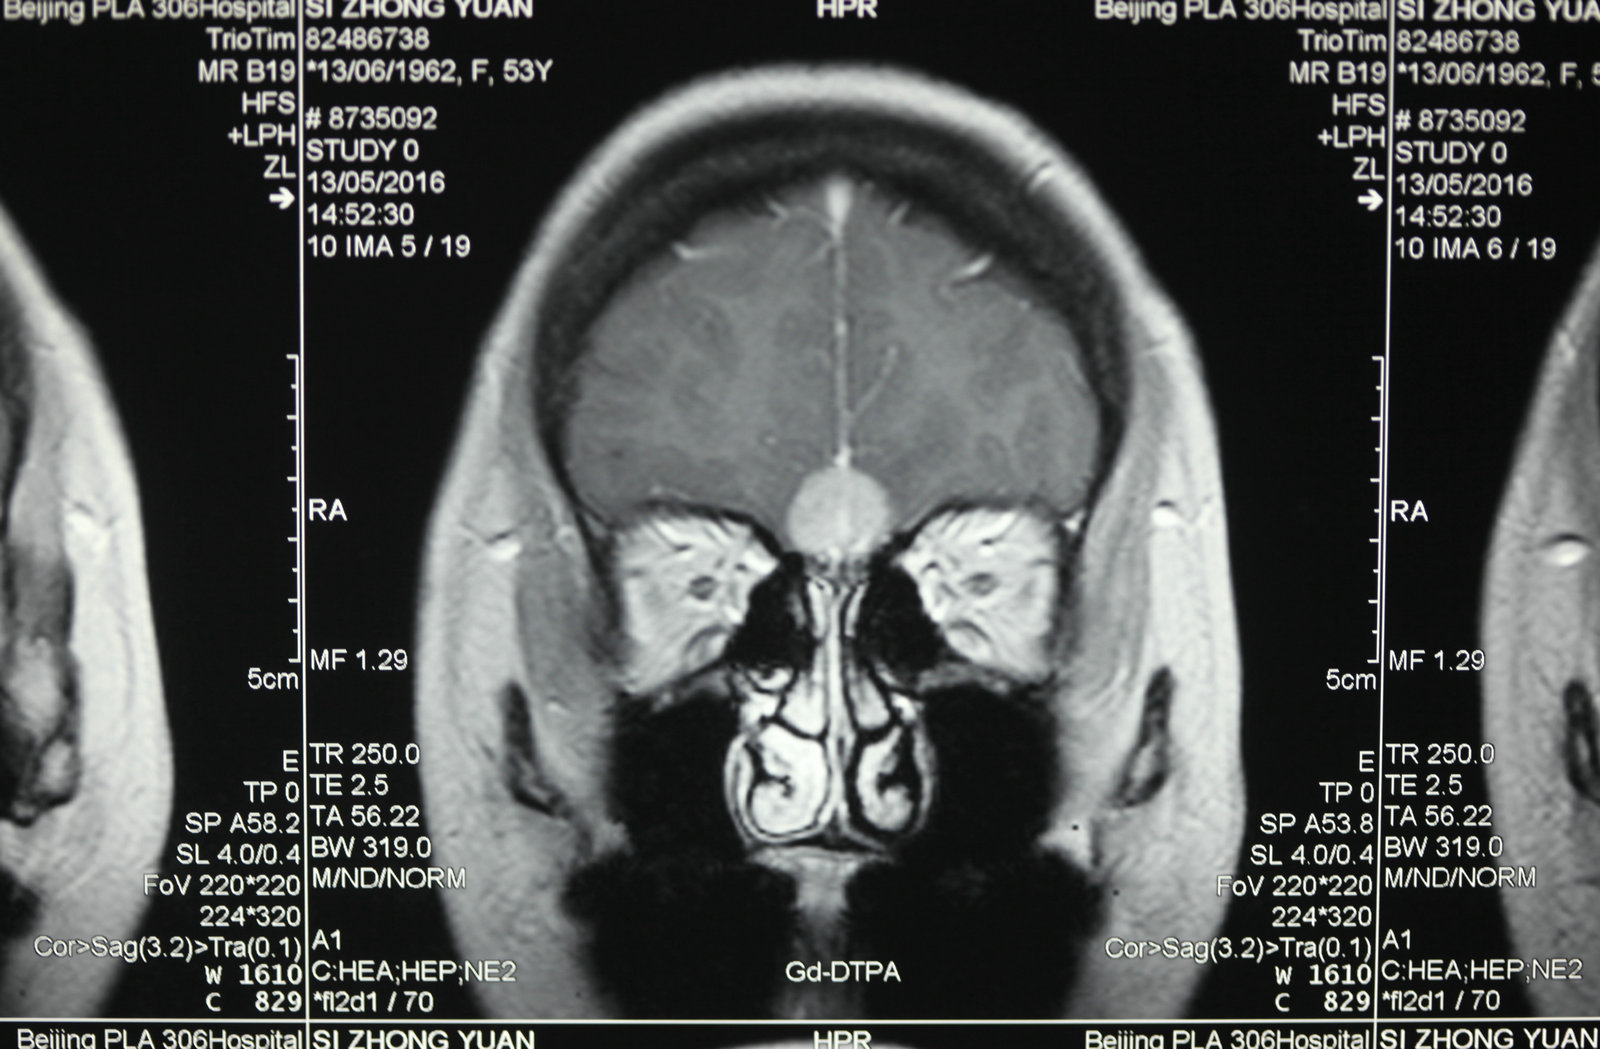

显微神经外科学是以应用手术显微镜为标志,但是,我们决不能片面的将显微神经外科学理解为只要手术中使用手术显微镜就是显微神经外科手术。而显微神经外科学的正确概念,足指以近代影像学为诊断基础,一整套与显微手术相匹配的手术设备、显微神经外科手术器械为保证的,以颅内病灶为中心的手术。显微神经外科学不仅是技术,更重要的是概念的更新。

将手术显微镜和显微神经解剖结合,会使许多常规的神经外科手术得到进一步完善,如脊髓的切除、动脉瘤的夹闭等,并开创了以往神经外科医生不能施行的手术。因为对显微神经解剖认识的深入,医生能够以较小的脑牵开或皮层结构切开,经过神经血管间隙,安全准确地达到脑深部病灶,进行微损伤的手术切除。总之,显微神经解剖和显微外科技术结合,可在微创下切除以往不能手术切除的病变。而应用手术显微镜进行神经外科解剖研究和神经外科教学是对以往的肉眼神经解剖研究的全新修正,它使肉眼观测困难的微小结构和纤细神经清晰可辨,属于全新的领域。 手术显微镜的应用又使医生感到手术操作在灵活性和精确性方面受限,因此又有学者开始探索机器人辅助手术,这将开创精细外科技术的新境界,当然它也要求有新的显微解剖知识与其适应。其他新技术的发展也需要以精确的显微神经解剖知识为基础,如在血管内栓塞治疗动脉瘤时,需要详尽了解载瘤动脉、穿通动脉及其解剖变异经过缜密的开颅设计,可达到颅底任何部位。将显微神经外科解剖研究结合影像学定位,利用脑表面的沟裂建立细小孔道,一些脑深部解剖能理想的显露。显微解剖研究也研究了一些新的手术入路,如经脉络膜入第三脑室手术入路、经鼻腔入蝶窦的垂体瘤手术入路等。在未来,通过更深入的显微外科解剖学研究,还会有一些新的更好的手术入路研究出来。另外一些新的手术技术的改进和完善也需要对显微外科解剖的深入理解。 随着神经精细结构显露技术的显著提高,显微解剖照片准确鲜明,生动活泼,非常优美,适合于神经外科学习和参考。